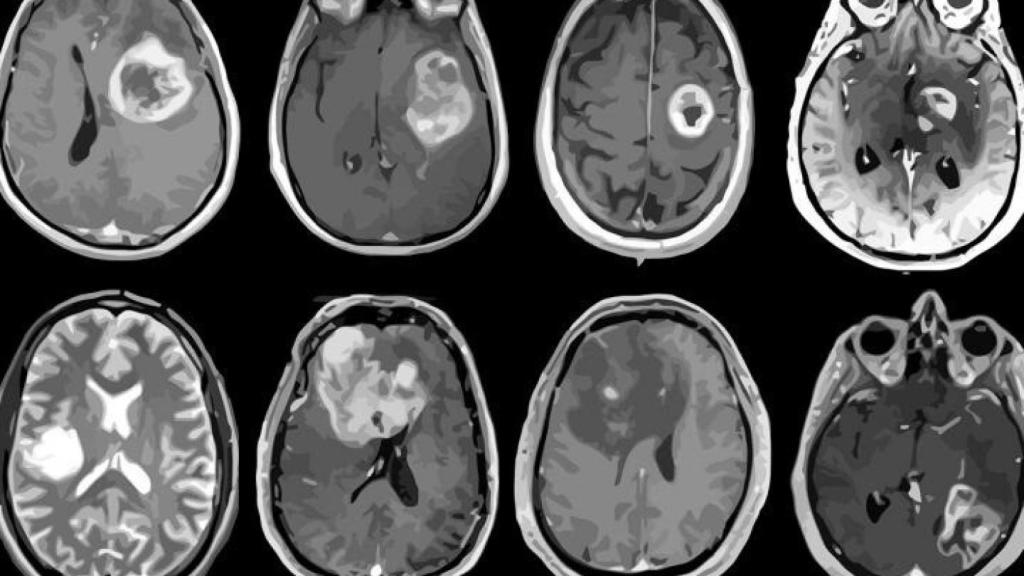

Los glioblastomas son los tumores cerebrales más frecuentes y más agresivos, con una tasa de supervivencia que apenas ha aumentado en los últimos 50 años, lo que pone de manifiesto la necesidad urgente de desarrollar nuevas estrategias terapéuticas. En la actualidad, el principal y casi único tratamiento para los glioblastomas es la combinación de radioterapia con el agente de quimioterapia llamado temozolomida, previa resección quirúrgica de la masa tumoral.

En el presente trabajo, los investigadores han puesto el foco en el fármaco dianhidrogalactitol, un quimioterápico que es capaz de atravesar la barrera hematoencefálica y alcanzar el sistema nervioso central , donde induce daño en el ADN de las células tumorales. Actualmente el dianhidrogalactitol está siendo testado en ensayos clínicos para gliomas y otros tipos de cáncer como el de ovario, y está ya aprobado en China para el tratamiento de la leucemia mieloide aguda y el cáncer de pulmón.